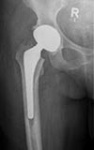

​Die Koxarthrose ist der Fachbegriff für die Abnutzungserscheinung des Hüftgelenkes. Typische klinische Zeichen sind das Auftreten von Schmerzen in der Leiste bis zum Knie sowie Bewegungseinschränkungen. Bei entsprechender Indikation erfolgt als operative Möglichkeit die Implantation einer Hüfttotalendoprothese (HTEP).

Hierbei handelt es sich um den Ersatz von Hüftpfanne und Hüftgelenkskopf. Die Implantate werden mit oder ohne Knochenzement verankert, je nach Knochenqualität. Je nach Grad und Art der Abnutzung des Hüftgelenkes steht eine Vielzahl von Implantaten zur Verfügung. Bei Eignung des Befundes wird eine minderinvasive Operationstechnik angewandt, welche zu einer geringeren Traumatisierung des Gewebes und einer schnelleren Mobilisierung der Patienten führt.

Koxarthrose

Hüfttotal-Endoprothese Kurzstiel-Endoprothese Normalstiel-Endoprothese